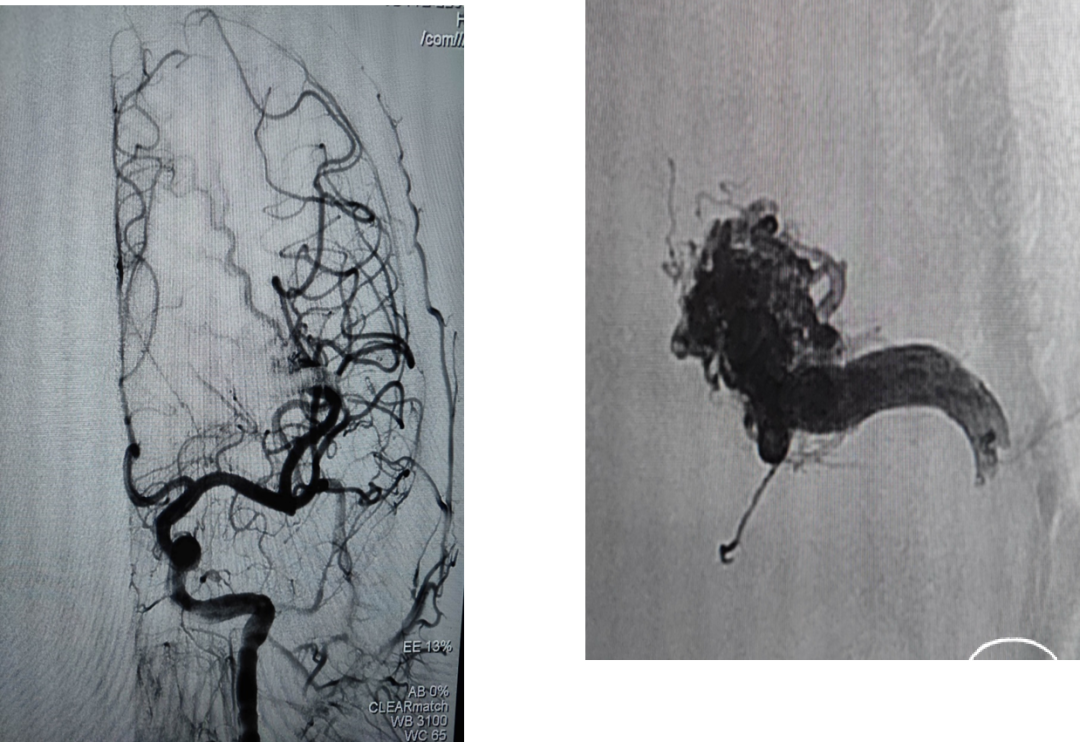

术前DSA

1、左侧额颞叶脑动静脉畸形

2、继发性癫痫

术中动脉造影

动静脉联合3d显示引流静脉与矢状窦关系;中天21微导管塑形(半圆)支撑下FATHOM-14导丝超选成功,考虑enchlon10长度不够,截断中管;FATHOM-14 3m交换enchelon10,但阻力大未能到位,中间管也未能到引流静脉入口;头羊作用下apollo3cm超选到位。

球囊保护静脉入路栓塞:注射onyx34约1ml,onyx18约1.5ml,总时长20min。

术后即刻造影畸形血管团不显影